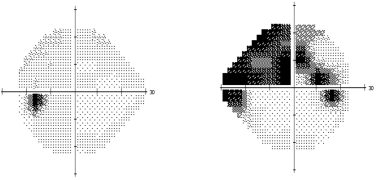

○ Campo visual